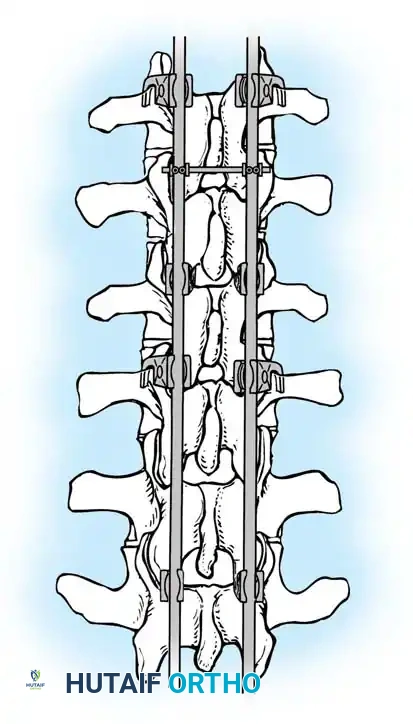

3. Pedicle Screw Instrumentation

Free-hand or navigation-assisted pedicle screws are placed bilaterally. High implant density is crucial at the apex (to allow for powerful reduction forces) and at the cranial and caudal foundations (to prevent pullout).

Postoperative AP radiograph demonstrating a well-aligned posterior pedicle screw construct.

Postoperative AP radiograph of an extended construct.